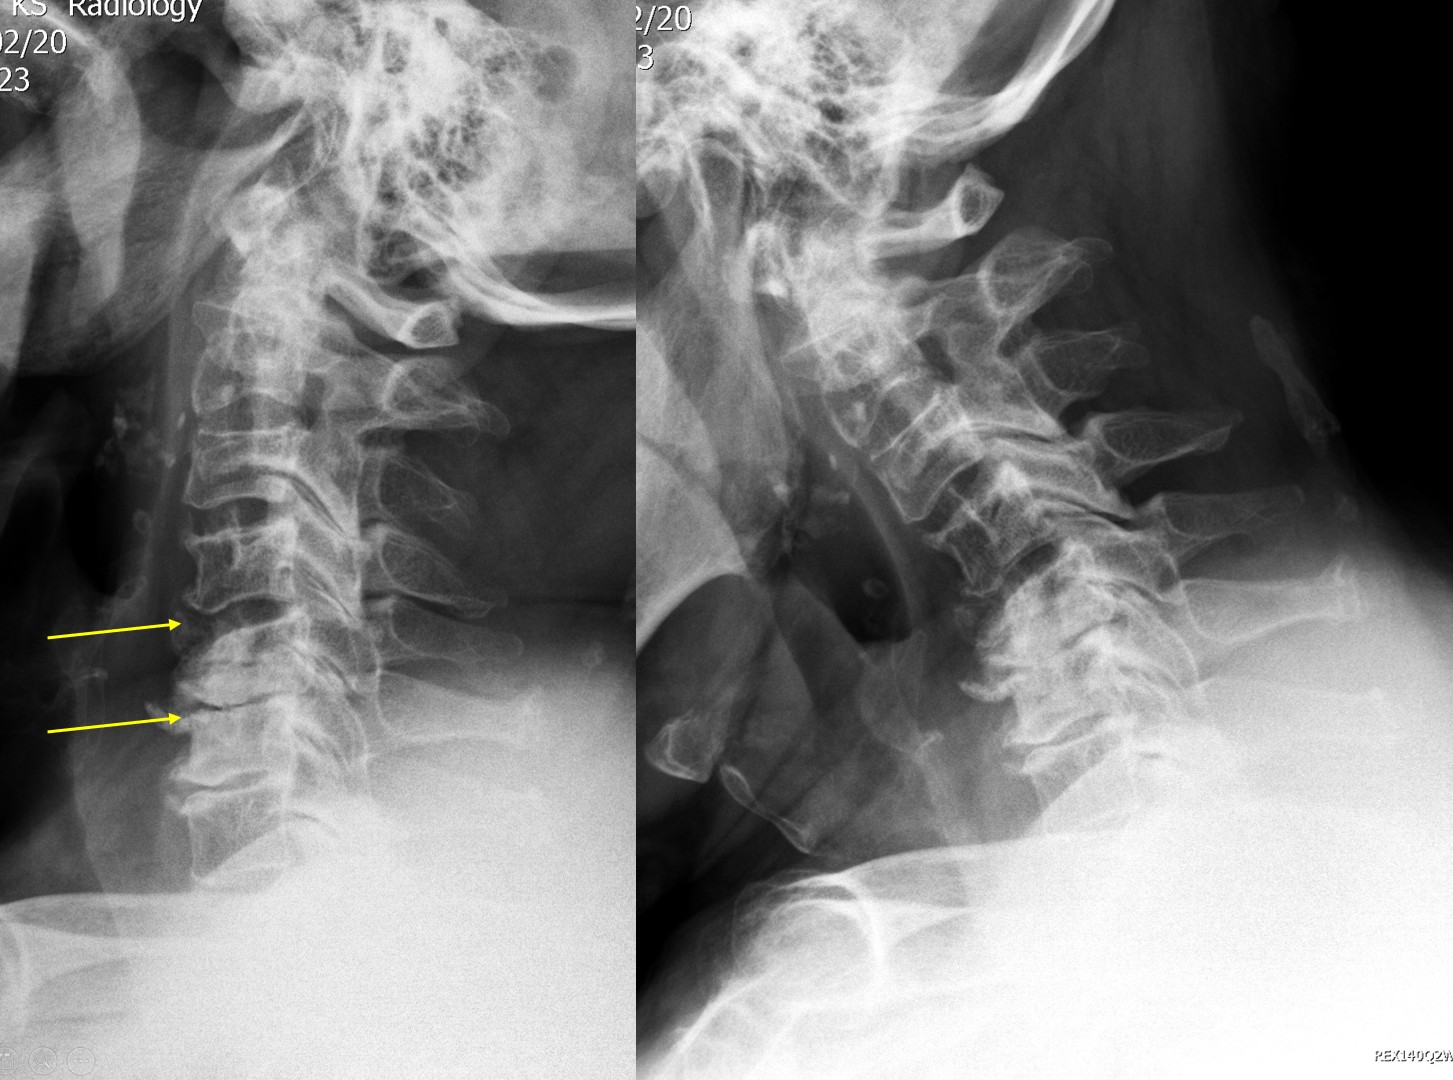

頸椎退化 (Cervical Spondylosis)

頸椎退化(Cervical spondylosis) 是一種隨年歲增長而出現的退行性病變,頸椎關節及軟骨受到重覆的磨損和損壞,長期勞損或欠缺運動造成頸椎椎間盤退化收縮 (Degenerative Disc)、頸椎關節之間生出骨刺 (Osteophyte)、頸椎骨間韌帶骨化(Ligament Ossification) 等不同情度的退化。

骨刺出現是關節退化警號,骨刺生長原意是要幫助關節分擔壓力,經擴大受力範圍,減少受壓點。骨刺本身不一定會引起痛楚,除非骨刺生長的位置,錯誤壓迫頸椎的神經根(即神經線),便可引起上肢麻痹、疼痛等症狀,痛楚可以由頸部伸延到手指。一旦壓着脊髓神經,可致手腳活動不靈活或無力,但患者未必會感到痹痛,或要以手術如脊髓減壓及頸椎融合手術治療。骨刺如非壓着神經根或脊髓神經,便不會帶來痛楚。